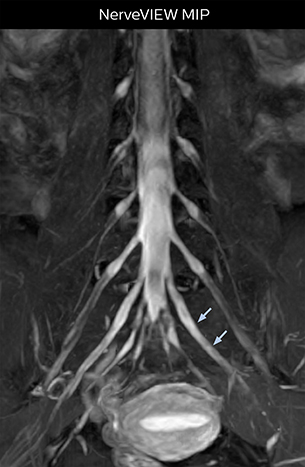

At Northern Fukushima Medical Center in Japan, excellent MRI visualization of nerves helps support confident diagnoses and informs surgical treatment decisions for patients with lower limb symptoms. MRI technologist Tanji and orthopedic surgeon Dr. Yabuki share how direct nerve visualization with the 3D NerveVIEW method adds information when diagnosing atypical herniations. The additional insights changed their way of working and benefit their patient care, as illustrated by some clinical examples.

“In patients with lower extremity neurological symptoms, NerveVIEW helps us to determine the disease matching the patient’s symptoms by directly visualizing the nerves. We use the sequence mainly, when there is suspicion of intraforaminal stenosis, extraforaminal stenosis or lateral disc herniation, which is often based on routine T2- and T1-weighted images. Additionally, the excellent depiction of the course of nerves makes NerveVIEW a good navigator when applying treatment such as block therapy or surgery.”

“In such case, we would then browse through axial T2-weighted MR images slice by slice and mentally reconstruct the actual situation based on both radiculography and MRI. Fortunately, NerveVIEW can now very well show nerve courses and presence of nerve compression or edema in one single image series.” “We have often seen NerveVIEW directly depict details of the nerve compression that were not observed by radiculography. Therefore, we think that with NerveVIEW we can reduce the number of invasive examinations, especially for some patients with lumbar plexus symptoms.”

“Before NerveVIEW, diagnosis by MRI alone was sometimes difficult, unless there was a strong suspicion based on clinical symptoms,” says Shoji Yabuki, MD, DMSc, Orthopedic surgeon at Fukushima Medical University School of Medicine. “This is why we routinely perform selective lumbosacral radiculography (nerve root block) and x-ray in such cases. However, radiculography can only depict nerves as far as the contrast agent reaches. When a nerve is distorted by compression, the contrast agent will not pass through this compressed area, preventing us from evaluating the full nerve compression.”

The key concept in MR neurography, Dr. Yabuki stresses, is the ability to directly visualize spinal nerves, versus inferring the presence of pathology indirectly. “Before NerveVIEW, we estimated compression of the nerve by looking for the presence or absence of fat signal on other MR images,” he says.

“For example, in sagittal images, when the presence of fat is observed in the intervertebral foramen, it suggests that there is a margin around the nerve. Similarly, the absence of fat indicates that the nerve is being compressed. So, we used to deduce nerve compression indirectly. With NerveVIEW, however, we can observe the condition of the nerves directly, regardless of the presence or absence of fat. We always prefer such direct observation of anatomy over having to make an inference about it.”

“NerveVIEW can clearly show nerve courses and presence of nerve compression. However, when multiple abnormalities are seen, it can still be hard to determine which nerve is causing the symptoms,” says Dr. Yabuki. “In our experience so far, we see abnormal findings on NerveVIEW in about 70% of elderly patients. As the pain is usually caused by only one nerve, we thus need to find the exact corresponding nerve.” “With a nerve root block, the patient's pain is improved by infiltration of local anesthesia directly around the nerve root considered to be responsible. Knowing such nerve root block findings prior to image interpretation, helps to easily recognize abnormal findings on NerveVIEW as well. In other words, without a priori knowledge, based on symptoms and/or nerve root block findings, we must be aware of the possibility of overdiagnosis.”